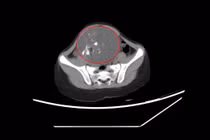

Trong ổ bụng người bệnh, có nhiều dịch mủ lẫn tóc, răng do khối u buồng trứng bên phải vỡ, kích thước khoảng 15 cm. Đồng thời, ê-kíp cũng phát hiện một khối u khác ở buồng trứng trái, kích thước 7cm.

Khối u buồng trứng chứa tóc và răng trong ổ bụng người bệnh - Ảnh BVCC